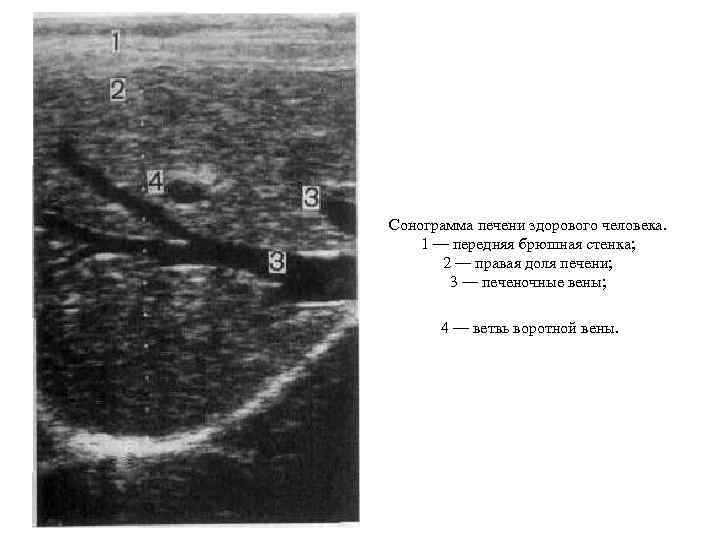

Сонограмма печени здорового человека. 1 — передняя брюшная стенка; 2 — правая доля печени; 3 — печеночные вены; 4 — ветвь воротной вены.